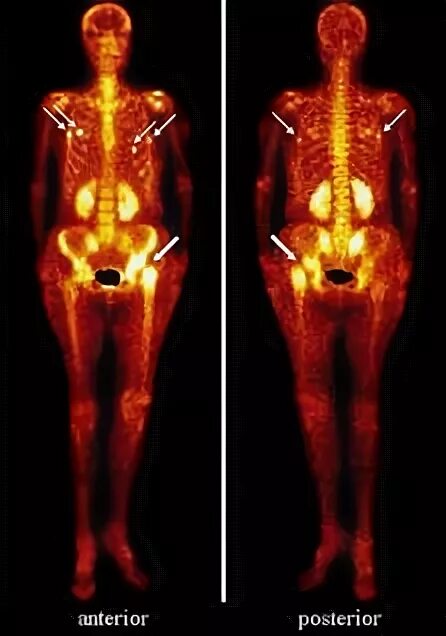

Метастазы скелета